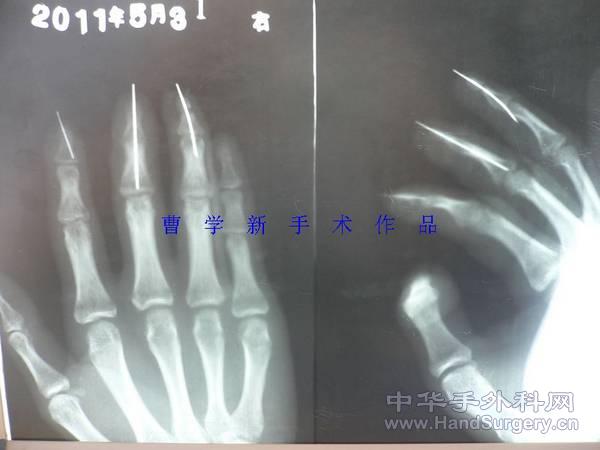

[断指再植] 双手五指完全离断再植(两年随访照来啦)

45天拔针后

RE: 双手五指完全离断再植(更新术后三个月随访)